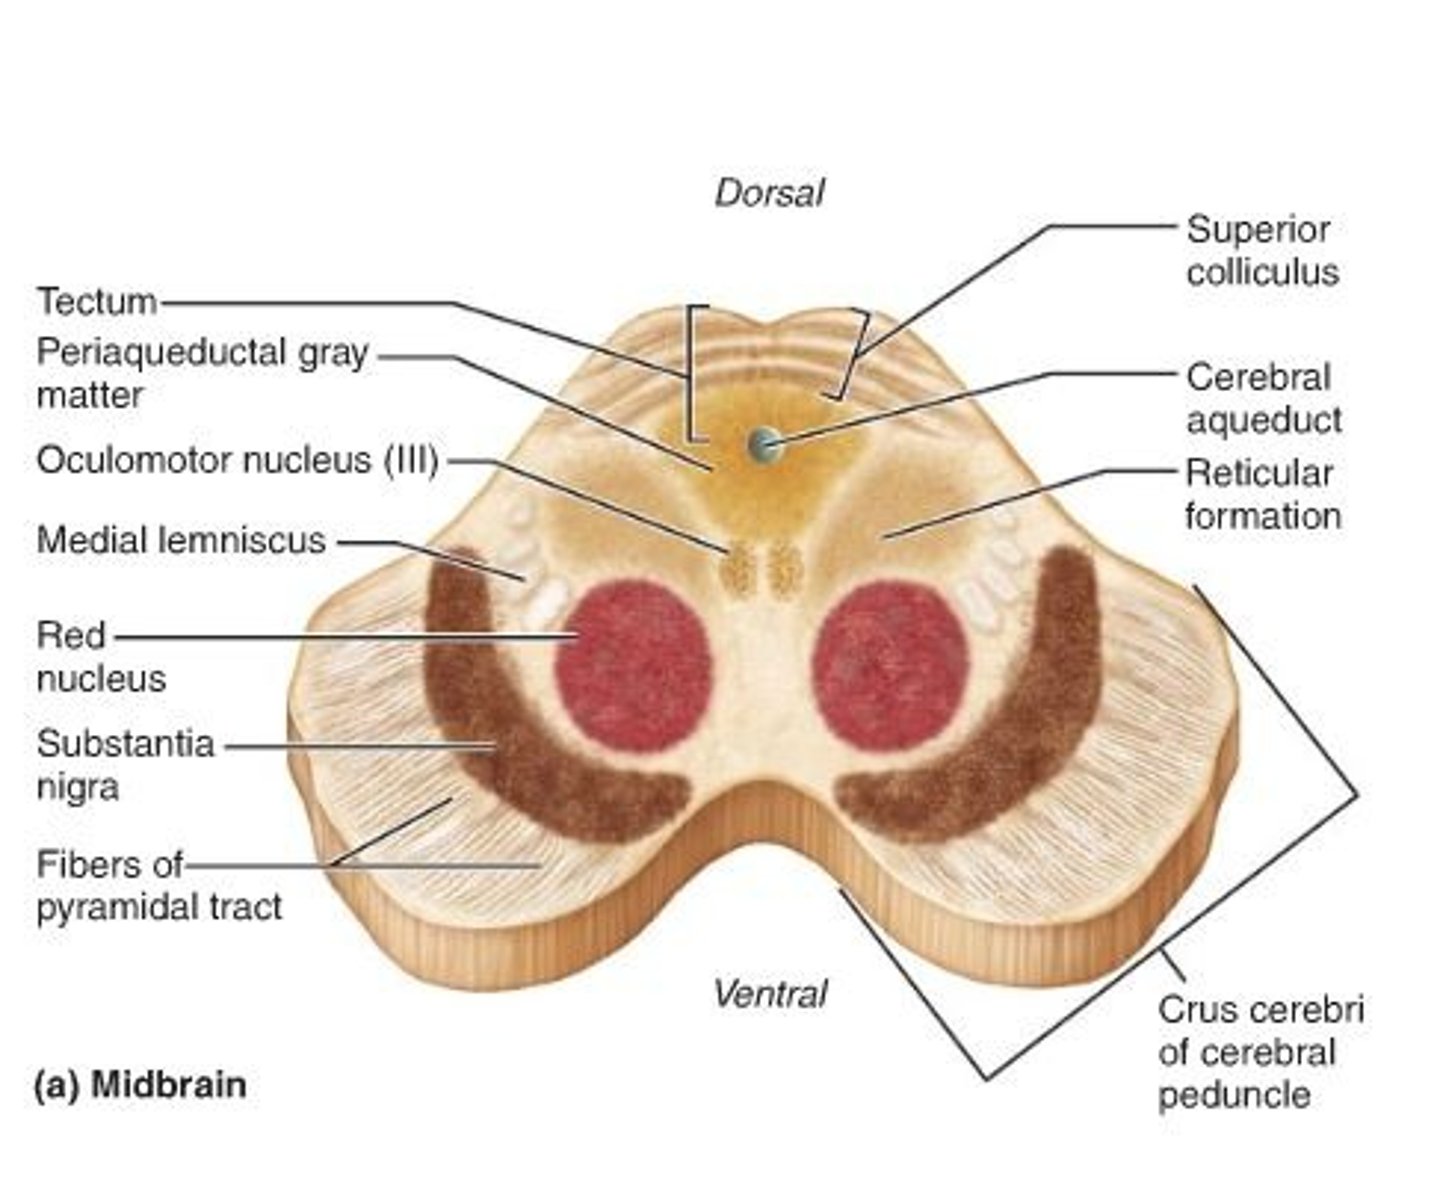

Mid brain

red nucleus

(red circle) - motor coordination

substantia nigra

Cerebral peduncles

interpeduncular fossa - space between cerebral peduncles.

Oculomotor Nerve (III) - narrows pupil and focuses lens